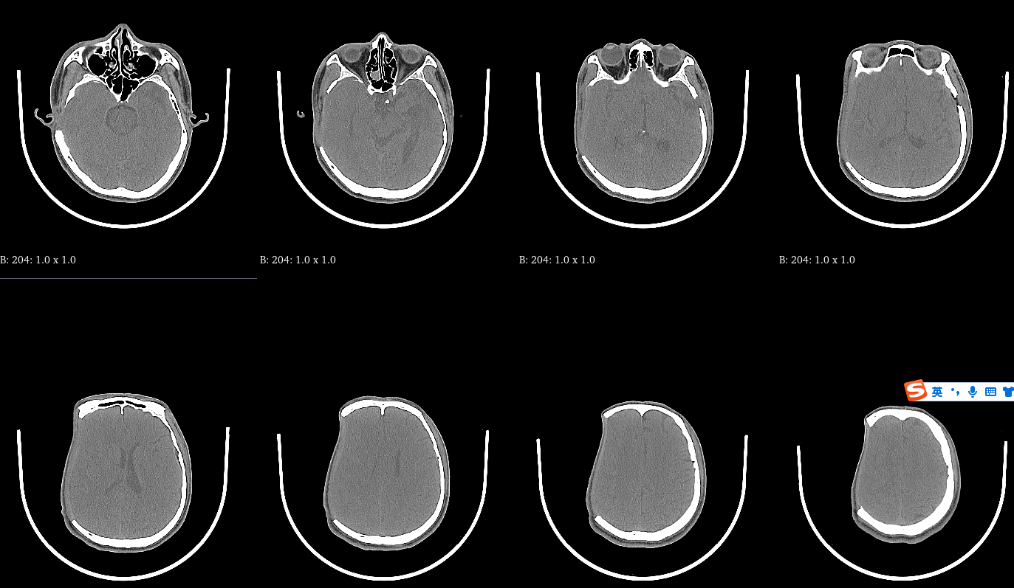

病例1:自体颅骨修补术前,去骨瓣术后2个月CT: